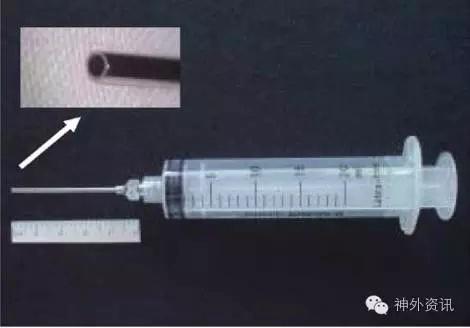

水分离技术(Water Dissection Technique)最早由匈牙利神经外科医师Toth在1987年提出,但却未得到应有的认可,直到近年来才得到广泛使用。水分离技术的方法其实很简单(见图1、图2、图3),手持20ml或50ml注射器+钝针头,对需要分离的界面不断冲洗和体温一致的生理盐水,延伸扩展裂隙空间,以进一步辨别分离。

图1. 水分离技术。(注:除图10外,余图均引自芬兰Juha Hernesniemi教授)

图2. 水分离技术。